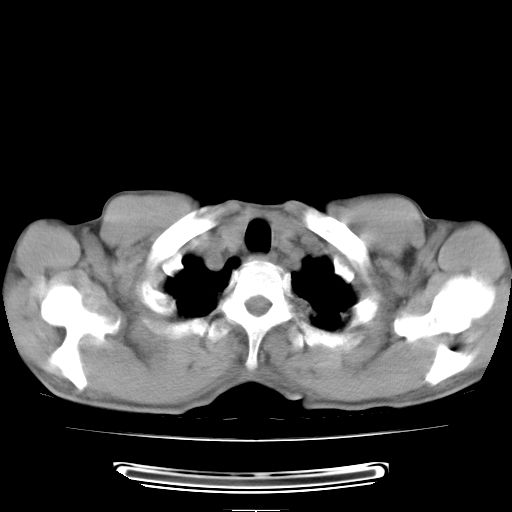

标题: CT25795:感冒后反复咳嗽两月余,痰中带血半月余。X诊断“肺 [打印本页]

标题: CT25795:感冒后反复咳嗽两月余,痰中带血半月余。X诊断“肺

1.双肺肺梗塞(理由:病灶呈三角形,与胸膜相连且局部胸膜肥厚,左心室增大)伴肺感染。

肺梗塞虽然有创意,但不现实。我考虑感染性病灶。

考虑两肺感染性病变,左肺上叶舌段肿瘤性病变待排;建议抗炎治疗后复查。